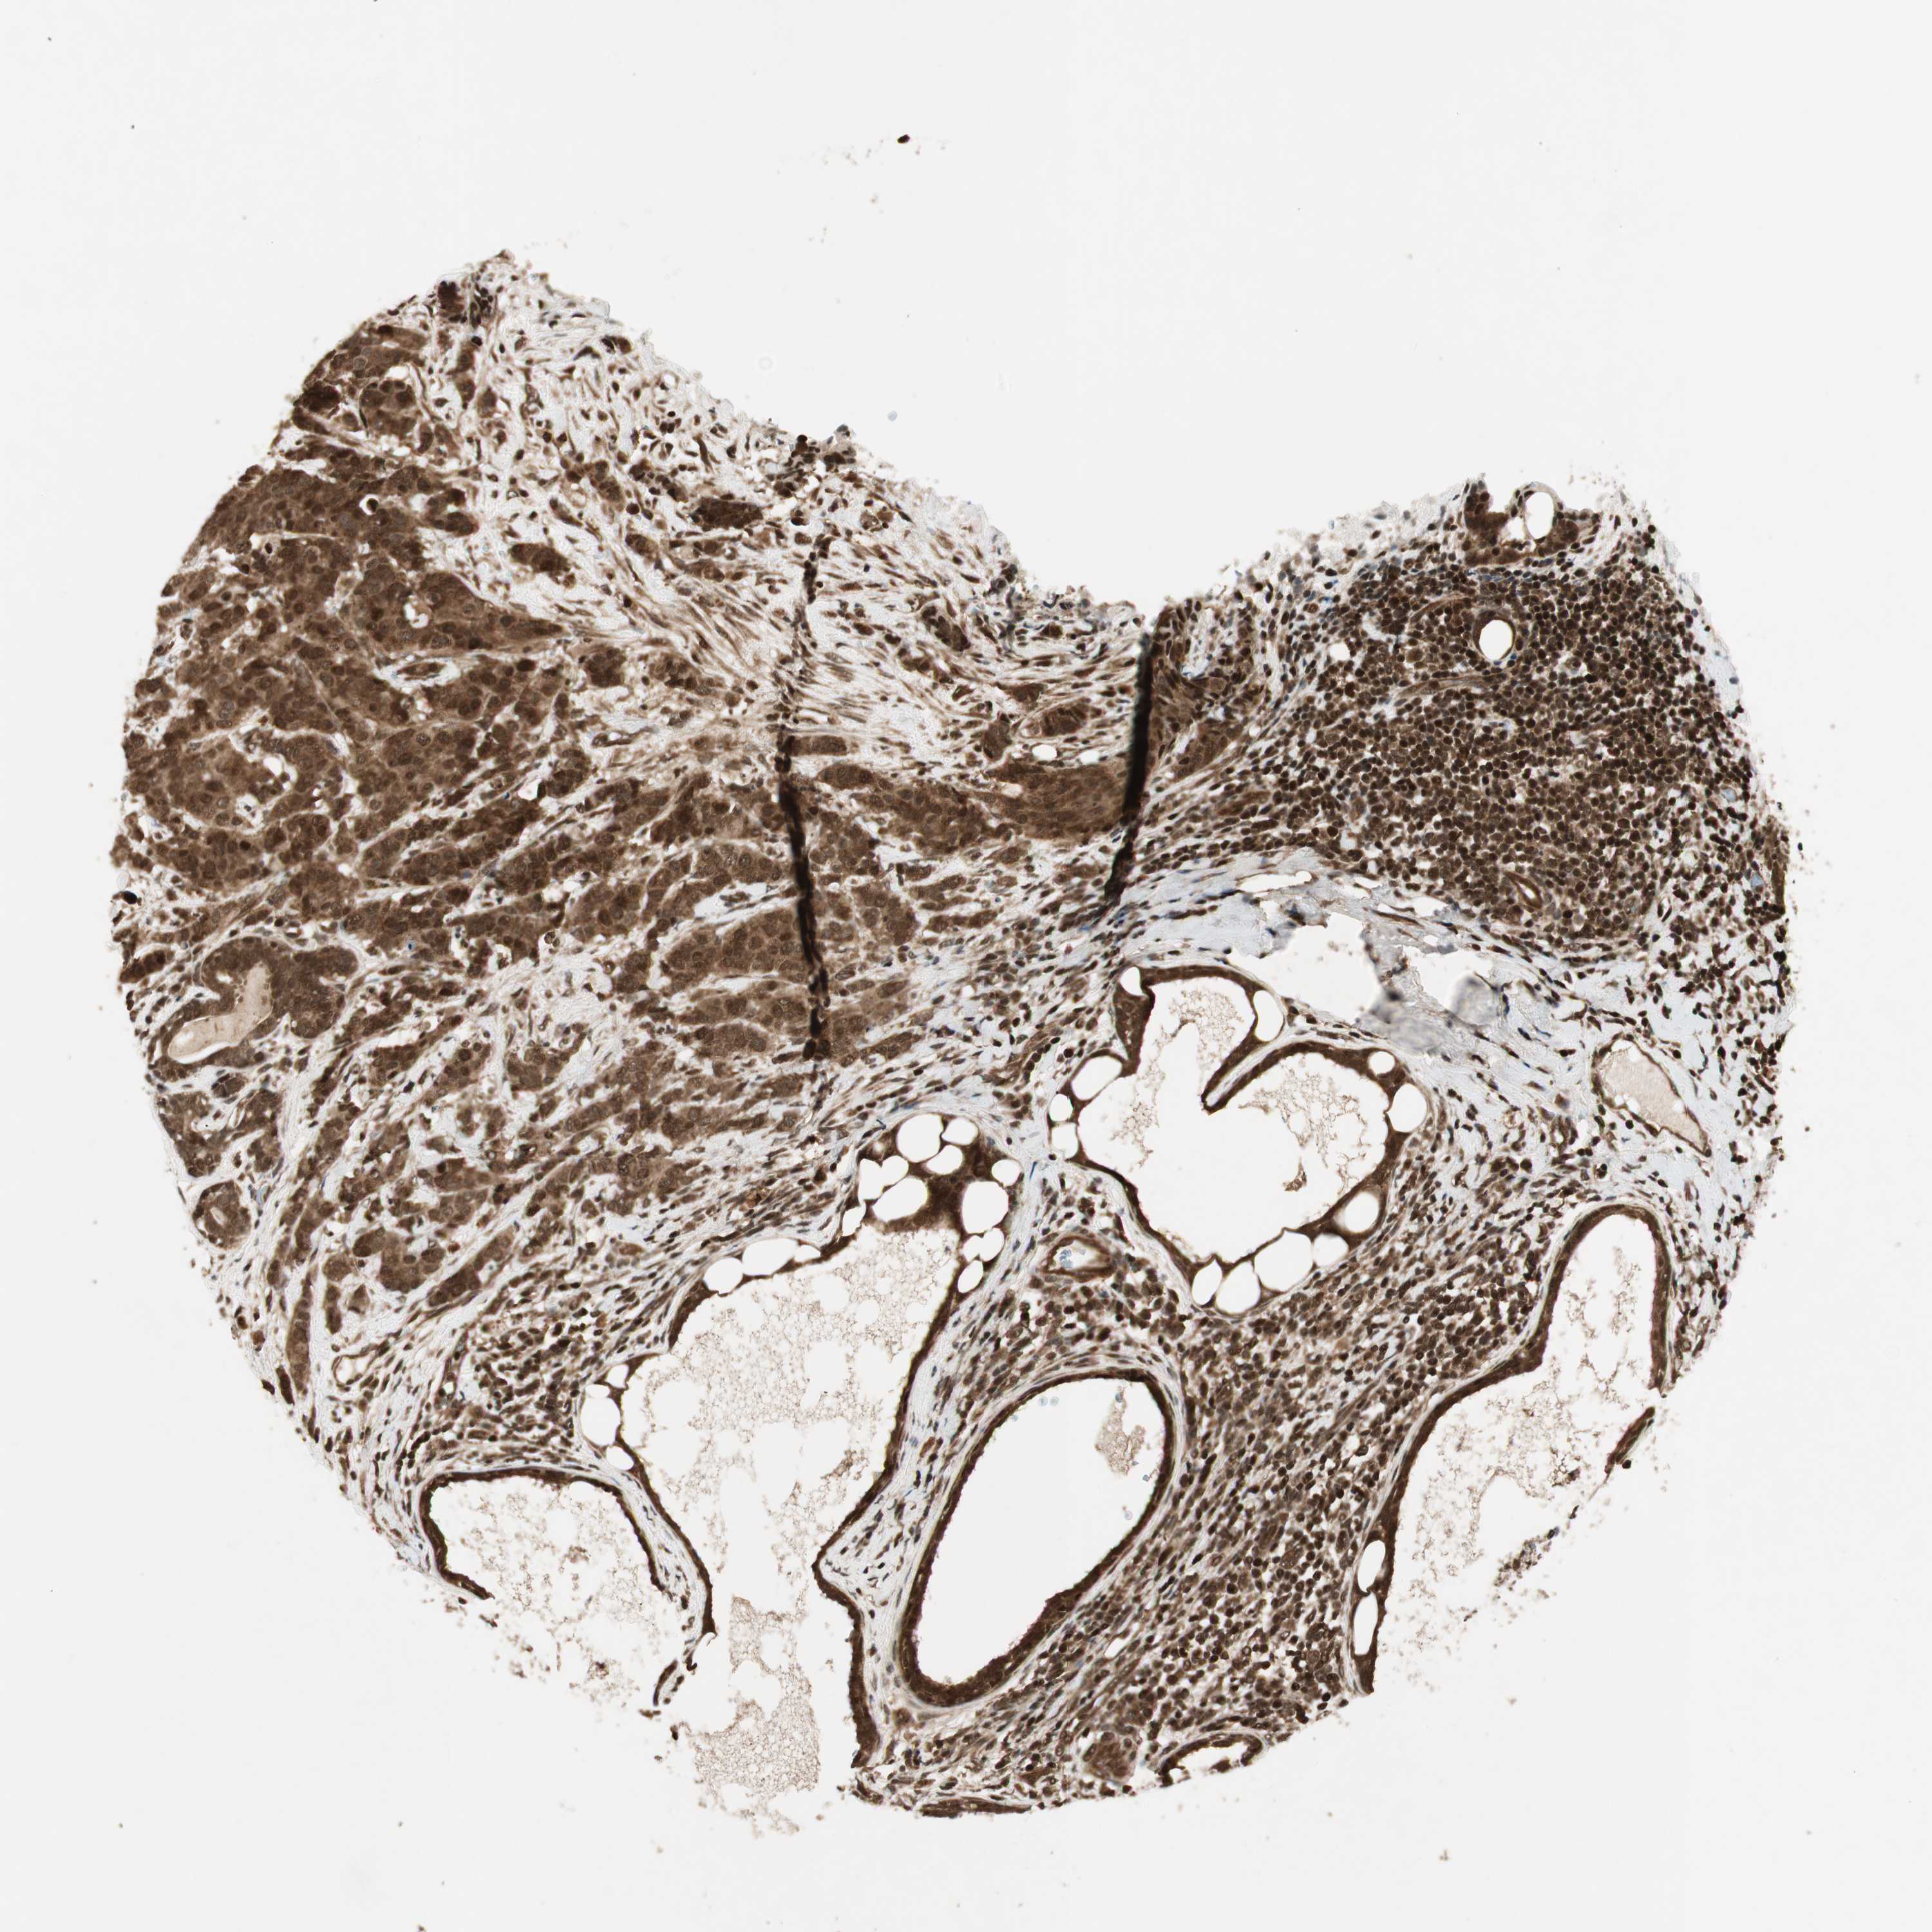

CANCER BREAST CANCER Show tissue menu

BRCA TCGA BRCA VALIDATION PROTEIN EXPRESSION

Breast cancer

Human cancer